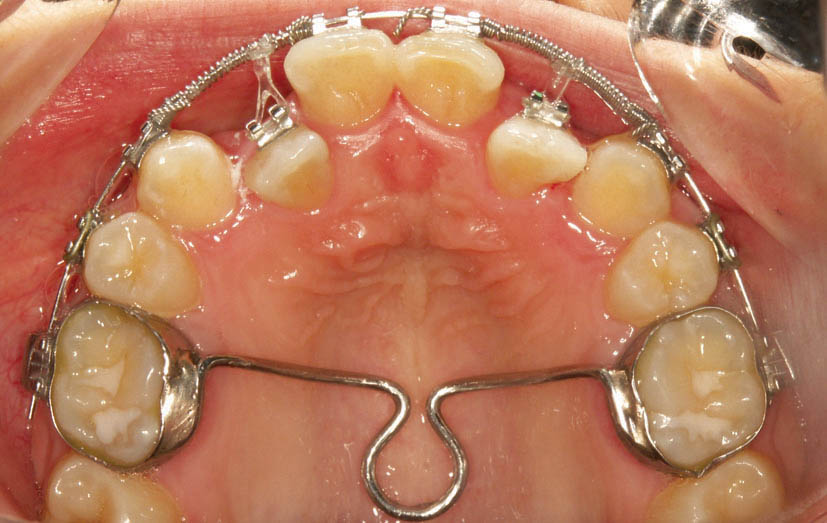

برای خارج کردن لترال از کراس بایت، به بایت پلیت خلفی نیازمندیم. اگر ارتودنسی فقط برای فک بالا انجام شده است برای فک پایین اسپلینت آکریلی میگذاریم (شکل 191-1) و اگر هر دو فک را ارتودنسی کردهاید مقداری کامپوزیت روی سطح اکلوزال دندانهای خلفی بگذارید تا بایت باز شود (شکل 192-1).

شکل 191-1: اسپلینت آکریلی روی فک پایین

شکل 192-1: بایت پلیت خلفی